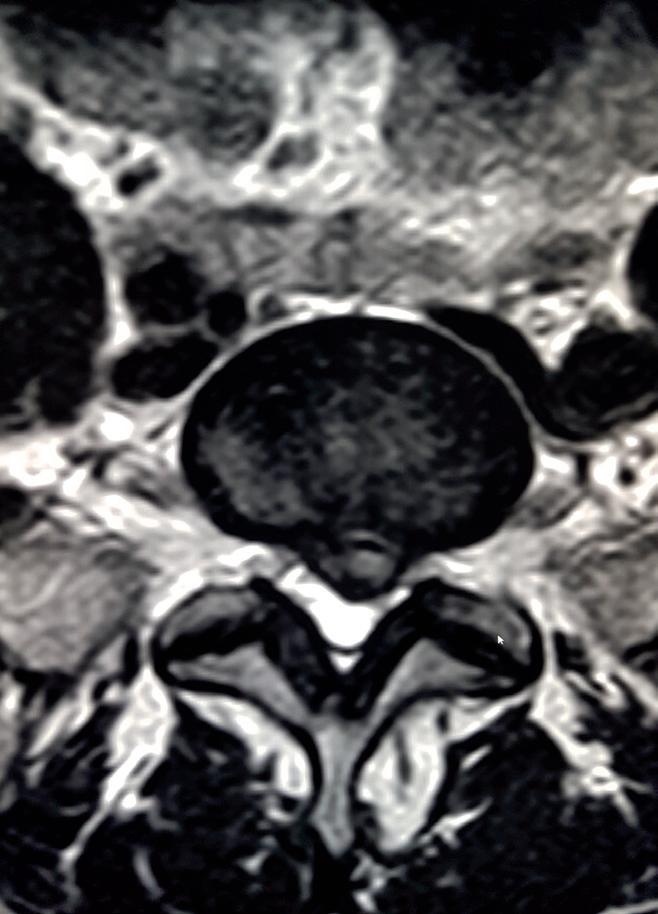

KURZ NOTIERT ... 66 IM INTERVIEW 68 Ladislav „Laci“ Legenstein WHO´S WHO 72 Boris Schwarz 3 FRAGEN – 3 ANTWORTEN 74 Timo Grober FIRMENPORTRAIT 76 Braun EDL PARTNERUNTERNEHMEN cook&more 80 epicto 82 HERZLICH WILLKOMMEN 84 KINDERSPORT 86 Kinder und Aufmerksamkeit LEISTUNGSSPORT & MEDIZIN 90 Sportmedizinische Untersuchung für die Leistungskinder und -jugendlichen der TARN